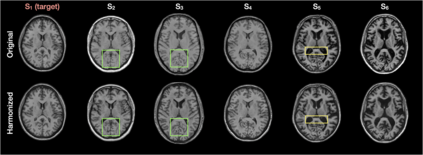

Disentangling anatomical and contrast information from medical images has gained attention recently, demonstrating benefits for various image analysis tasks. Current methods learn disentangled representations using either paired multi-modal images with the same underlying anatomy or auxiliary labels (e.g., manual delineations) to provide inductive bias for disentanglement. However, these requirements could significantly increase the time and cost in data collection and limit the applicability of these methods when such data are not available. Moreover, these methods generally do not guarantee disentanglement. In this paper, we present a novel framework that learns theoretically and practically superior disentanglement from single modality magnetic resonance images. Moreover, we propose a new information-based metric to quantitatively evaluate disentanglement. Comparisons over existing disentangling methods demonstrate that the proposed method achieves superior performance in both disentanglement and cross-domain image-to-image translation tasks.